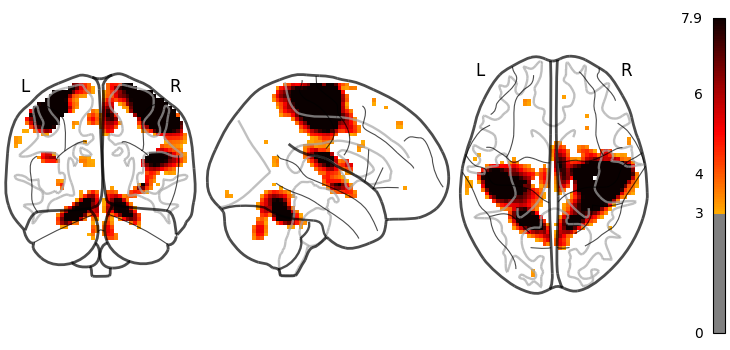

Data mining / exploration

Data-driven exploration of brain images. This includes the extraction of the major brain networks from resting-state data (“resting-state networks”) or movie-watching data as well as the discovery of connectionally coherent functional modules (“connectivity-based parcellation”). For example, Extracting functional brain networks: ICA and related or Clustering to parcellate the brain in regions with clustering.